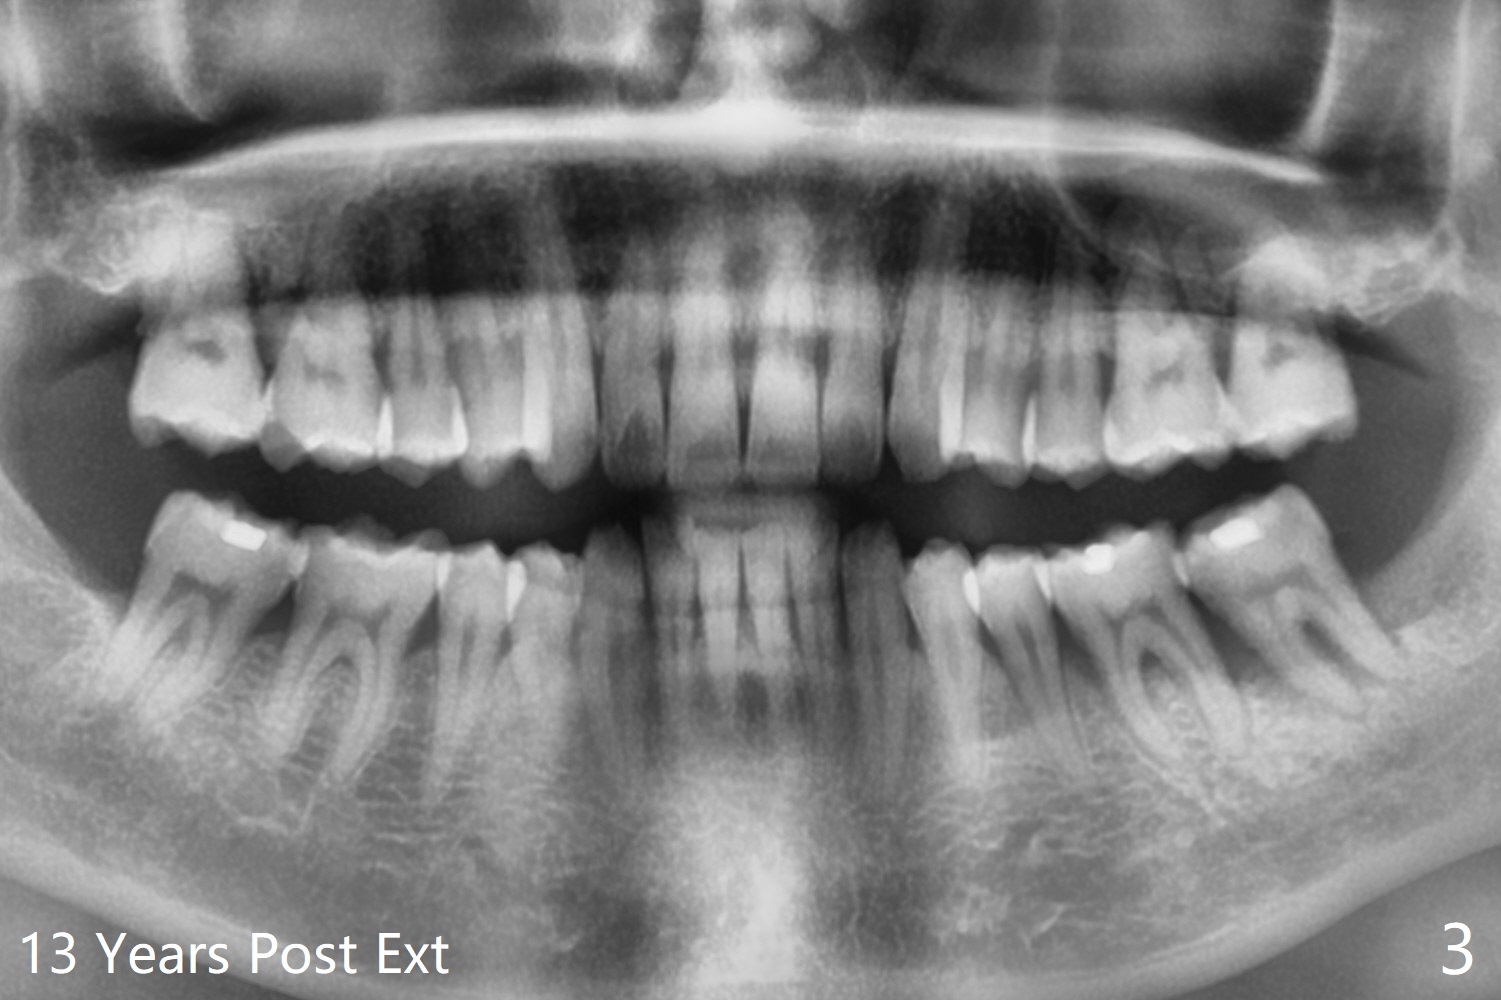

第二第三磨牙之间无骨

55岁男13年前就诊深洗同时拔除左下智齿(第二第三磨牙之间无骨,图一),拔除后没有植骨。十年后第二磨牙远中出现骨缺损(图二),十三年后第二磨牙松动(图三),需要拔除种植(图四)。其实当年拔除后必须植骨(图一’:红色 (白色:膜或者塞)),甚至种植(图一”:绿色),植骨。Thirteen years post #17 extraction, the lingual plate (L) is lower than the buccal one (B). Return to Prevent Molar Periimplantitis (Protocols, Table) No Caries No Antibiotic Plug 提升 手术 Xin Wei, DDS, PhD, MS 1st edition 03/27/2021, last revision 05/31/2021